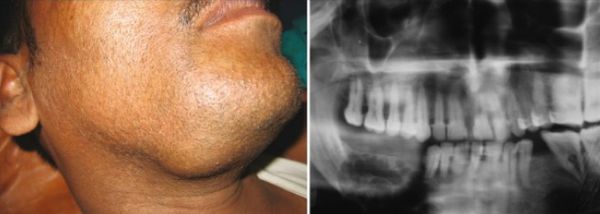

Амелобластома (Ameloblastoma) — это доброкачественная опухоль, которая развивается из зубообразующих тканей. По мере её роста деформируются черты лица, смещаются и расшатываются зубы.

Амелобластома развивается медленно и бессимптомно, чаще возникает в области угла и ветви нижней челюсти. Почти никогда не вызывает воспаления.

Чаще всего амеобластома возникает в области угла и ветви нижней челюсти, в области зубов мудрости [9] . На ранних стадиях заболевание протекает без симптомов.

Амелобластома относится к доброкачественным опухолям, которые развиваются внутри кости нижней челюсти. Как правило, она растёт медленно [10] . Если болезнь не лечить, то расшатываются и смещаются зубы, деформируется прикус. В дальнейшем, при достижении больших размеров опухоли, нарушается симметрия лица. Таким пациентам требуются обширные хирургические вмешательства и длительная реабилитация.

Развитие амелобластомы происходит очень медленно, и пациент длительное время может не замечать никаких симптомов. Однако с прогрессированием заболевания челюсть деформируется. Первым видимым проявлением болезни служит нарушение симметрии лица, припухлость со стороны поражения. Нужно отметить, что степень асимметрии может различаться: от небольшой до значительно выраженной. Амелобластома верхней челюсти встречается гораздо реже, но может протекать еще более незаметно визуально, поскольку опухоль распространяется в верхнечелюстную пазуху.

Когда опухоль начинает повреждать структуру костной ткани, у пациента появляется боль, которую он может принимать за зубную. Происходит расшатывание и смещение зубов. Челюсть в месте поражения постепенно деформируется, а при дальнейшем прогрессировании патологии истончается кортикальная пластинка – появляется характерный пергаментный хруст. При пальпации определяется гладкий или бугристый веретенообразно вздутый участок кости, при истончении костная ткань легко прогибается и пружинит. Со стороны полости рта можно наблюдать деформацию альвеолярного отростка.